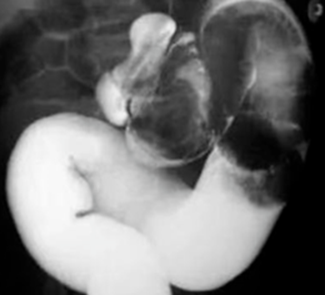

空气灌肠或钡灌肠:空气、钡剂于套叠部位受阻、造影剂与套叠肠管交接部形成“杯型”及软组织包块影。

小肠型、结肠型的套入部即套头一般呈单一的弧形, 在气体衬托下呈杯口状(图示)